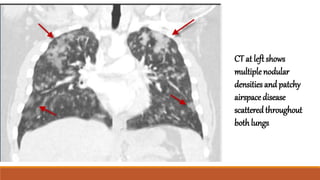

CT scan demonstrates multiple small cavities within an

area of pulmonary contusion.

CT scan demonstratesmultiple small cavities within an area of pulmonary contusion.